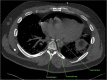

An esophagopericardial fistula developed in a 33-year-old patient after radiofrequency ablation for atrial fibrillation. He was initially managed with an esophageal repair and a left atrial bovine pericardial patch and eventually an esophagectomy. At 6-month follow up he had no symptoms. The case highlights the complexities of managing this life-threatening complication. (Level of Difficulty: Advanced.).